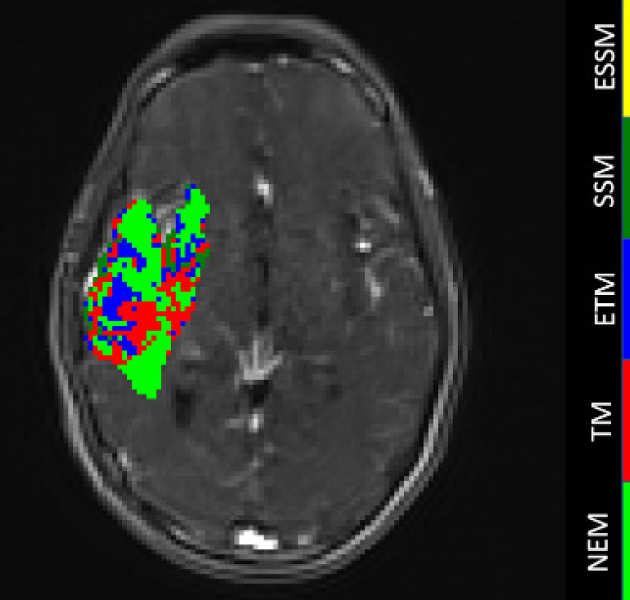

Multiparametric analysis of brain tumours

We are investigating the integration of different imaging (DCE-MRI, DWI-MRI, DSC-MRI and PET) techniques for the characterization of tumour tissue.

We are investigating the integration of different imaging (DCE-MRI, DWI-MRI, DSC-MRI and PET) techniques for the characterization of tumour tissue.